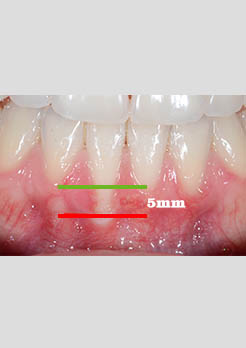

Enxerto Gengival Niterói

Antes e Depois